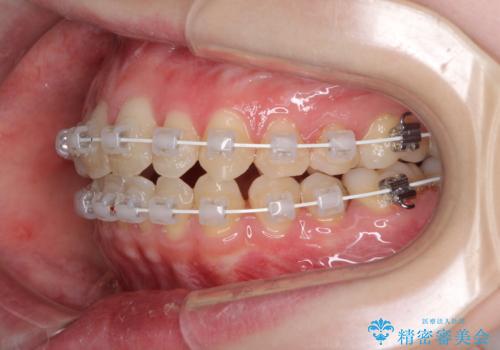

- 矯正装置

- 審美装置

治療途中で出産されたこともあり、当初予定よりも終了までに期間がかかってしまいました。

舌を前方に突出する癖があったため、上下前歯がなかなか接触しなかったことも治療期間が伸びた要因です。